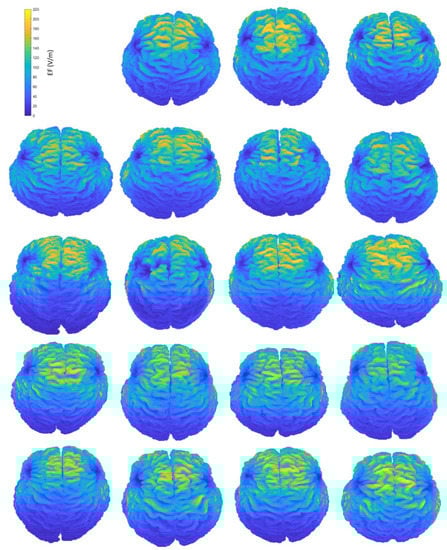

Figure A3.

Interindividual variability of the induced EF distributions visualized on subjects’ homogeneous brains, containing both grey and white matter, when the coil is placed at central position.